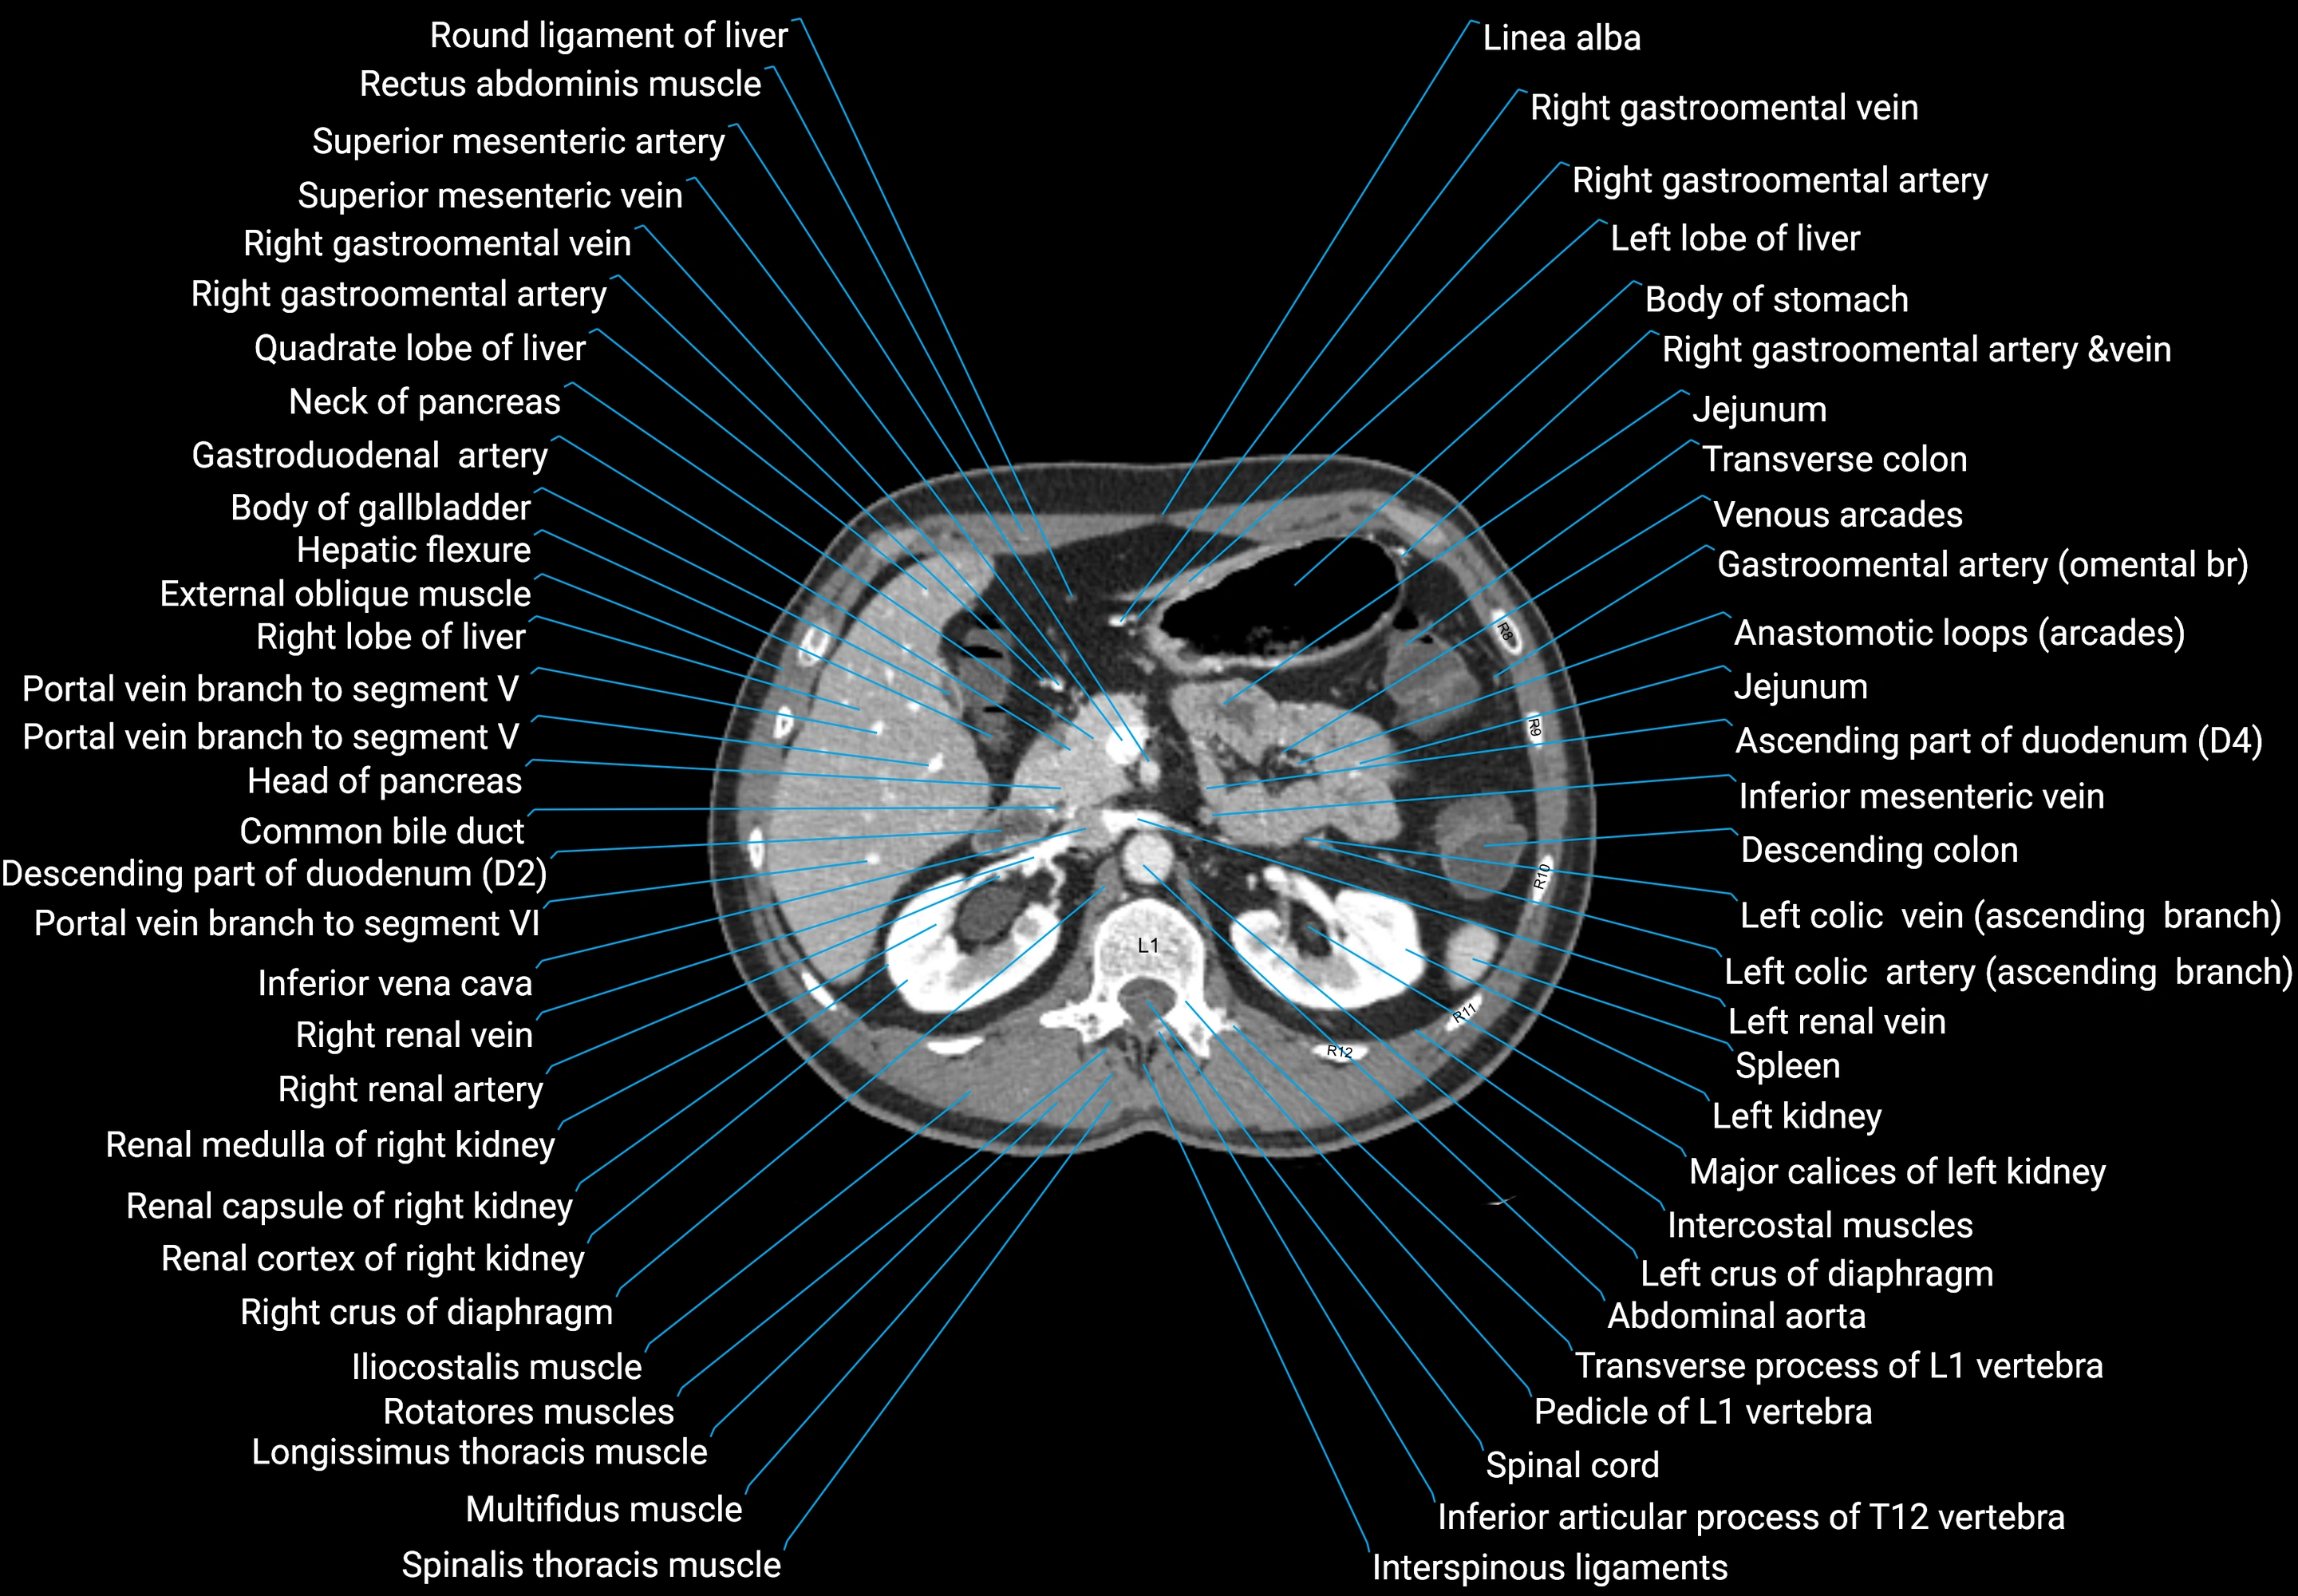

CT images